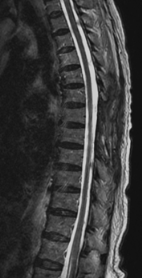

胸椎黄色靱帯骨化症を認め脊髄を圧迫している状態です。骨化部分を切除することで脊髄の圧迫を解除し症状は改善しています。